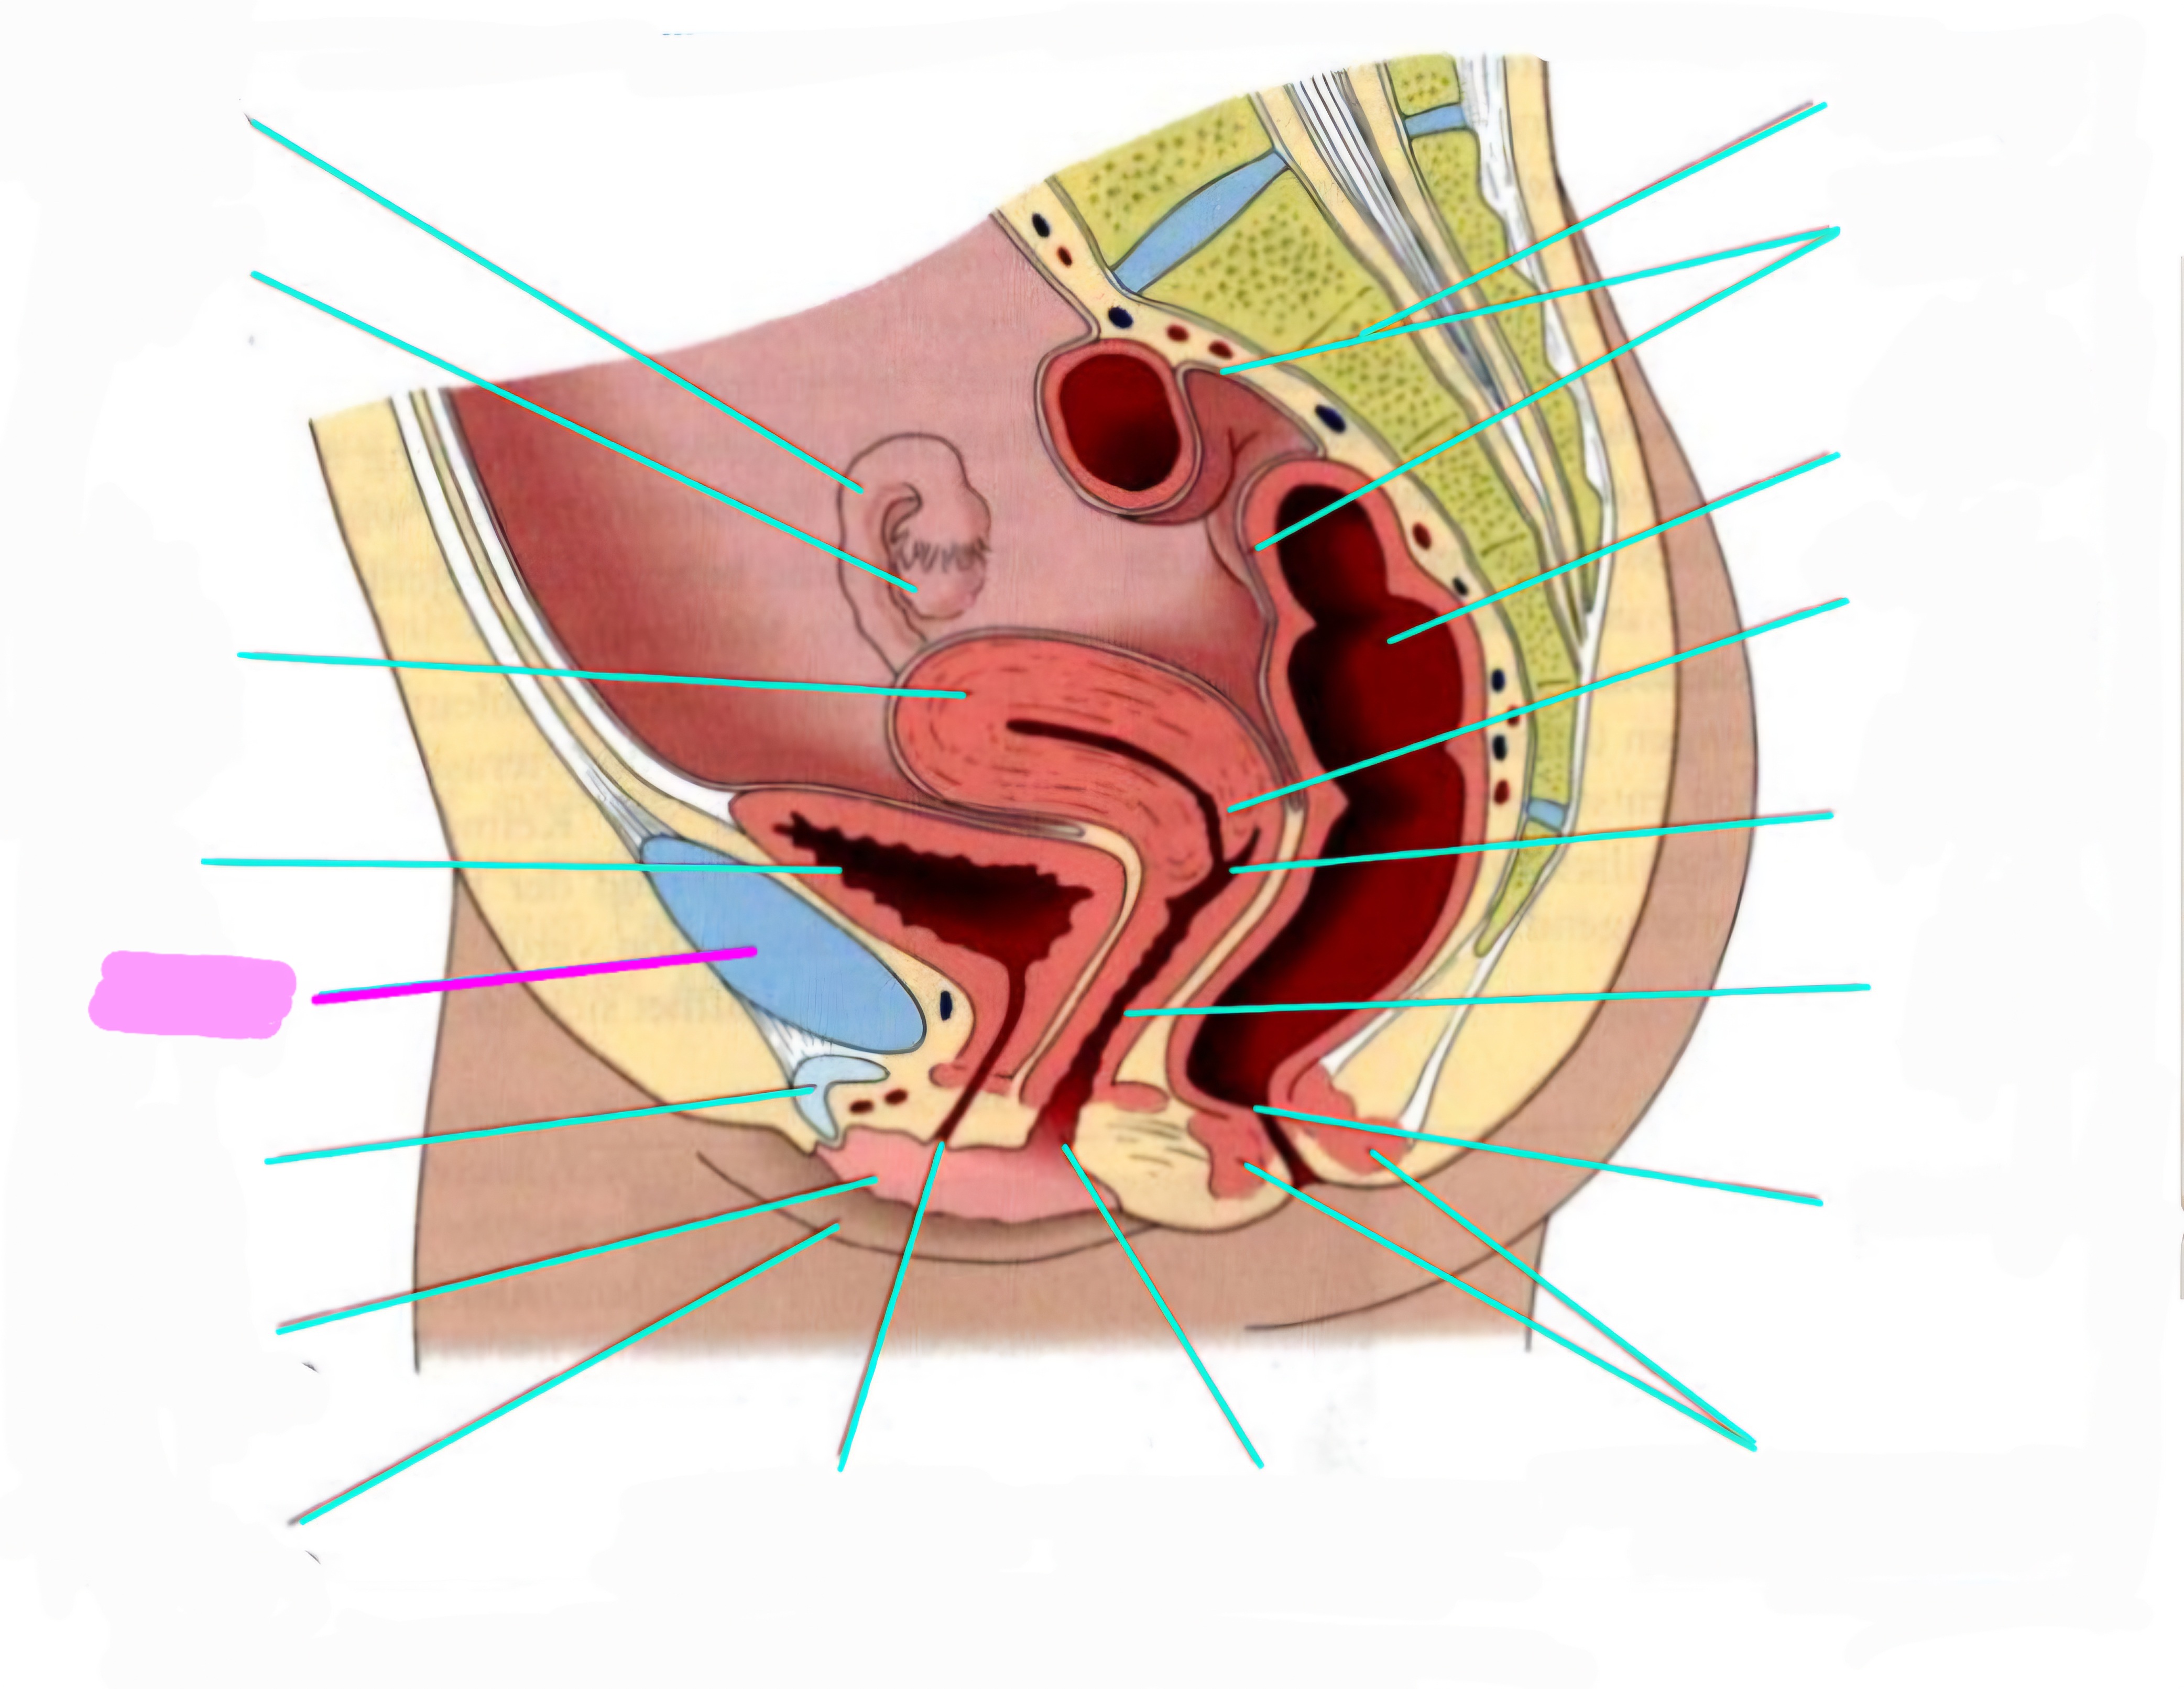

wbl. genital Anatomie

19 Terms

Tubea uterina (Eileiter)

Ovar (Eierstock)

Uterus (Gebärmutter)

Vesica Urinaria (Harnblase)

Symphyse

Klitoris

Labia minor pudendi (kleine schamlippen)

Labia Majoran pudendi (große Schamlippe)

Urethra (Harnröhre)

Introitus vaginae (Scheideneingang)

Sphincter ani externes (äußere Afterschließmuskel)

Anus (After)

Vagina (Scheide)

Portio (äußerer Muttermund)

Rektum (Mastdarm)

Zervix (Gebärmutterhals)

Peritoneum (Bauchfell)

Os sacrum (Kreuzbein)